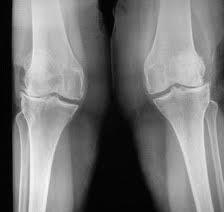

1

Q

Describe deformity seen. When performing TKR to either knees, how would you perform soft tissue balancing for correction of this deformity?

A

There is varus deformity, a coronal plane deformity.

There is concave (ST tight) and convex side (ST loose/strecthed).

Always start with tight side/ concave side first, which is medial side in this deformity.

Sequence of medial compartment release

1. Osteophytes

2. Deep MCL & Medial knee capsule

3. Posterior Medial Corner - capsule, semimembranosus.

4. Superficial MCL

i) Posterior oblique portion - if medial extension tightness

ii) Anterior portion - if medial flexion tightness

2

On this xray, there is valgus deformity in the coronal plane.

There is concave (ST tight) and convex side (ST loose/stretched).

Always start ST release at the tight side/ concave side first, which is lateral side in this deformity.

With the knee in extension

Sequence of lateral compartment release

2. Lateral capsule

3. Iliotibial band - tight in extension

then flex the knee

4. Popliteus - tight in flexion

5. Lateral collateral ligament - always last